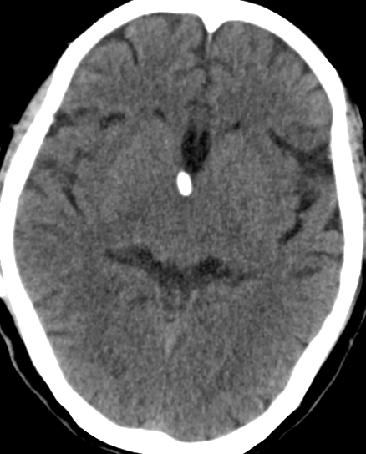

2013-8-2 CT

腰穿脑压240